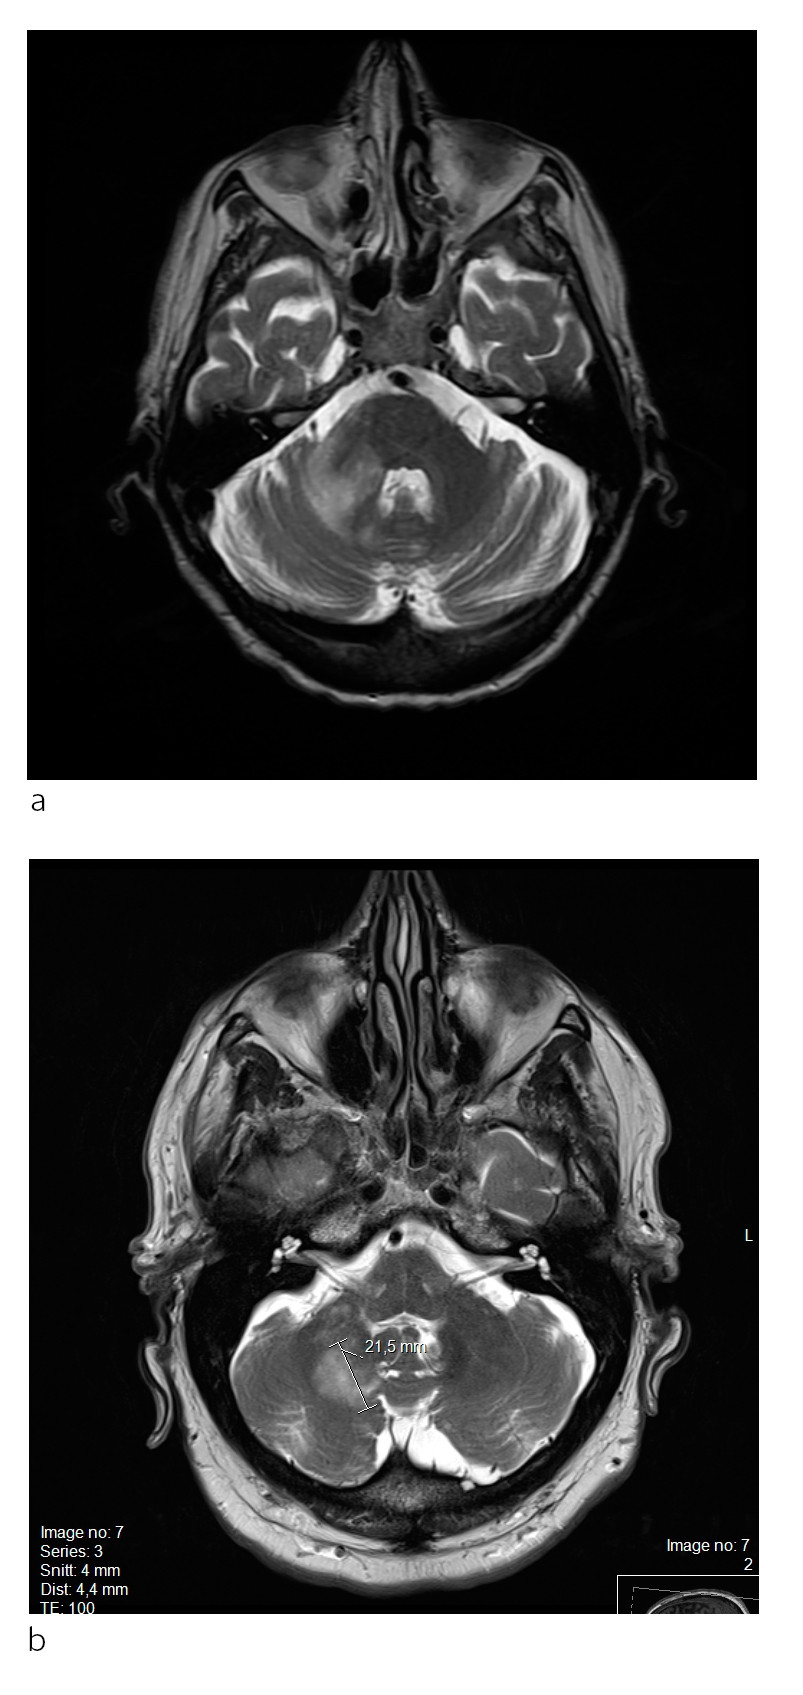

Pasient 1. En mann i 60-årene med kjent kronisk lymfatisk leukemi ble innlagt på grunn av kraftsvikt i venstre arm, kognitive vansker og problemer med dagligdagse gjøremål. Ved klinisk undersøkelse fremsto han som motorisk og mentalt langsom, og han hadde problemer med å samarbeide. Man fant en lett spastisk venstresidig hemiparese.

Det ble gjort CT- og MR-undersøkelse (fig 1). PCR-undersøkelse av JCV-DNA viste store mengder med viruset i spinalvæsken: 4,1 milliarder kopier/ml. Spinalvæskeundersøkelsen for øvrig var normal. Pasienten fikk humant immunoglubulin intravenøst (Octagam), men ble gradvis dårligere og døde i sykehus etter noen uker.

Ved mistanke om progredierende multifokal leukoencafalopati skal det gjennomføres MR-undersøkelse. Forandringer kan ses i hjernens hvite substans som multiple små lesjoner og/eller større konfluerende områder hvor som helst i storehjernen, oftest subkortikalt (fig 1), og i lillehjerne og hjernestamme (fig 3). Signalforandringer i ryggmargen bør gi mistanke om annen lidelse, men kan angivelig forekomme ved progredierende multifokal leukoencafalopati, men svært sjelden (20). Normale MR-bilder utelukker vanligvis tilstanden, men ved vedvarende klinisk mistanke bør undersøkelsen gjentas.

Diagnostikken kan være utfordrende hos pasienter med multippel sklerose, da grunnsykdommen i seg selv gir varierende nevrologisk utfall og multiple lesjoner i hvit substans, og den lar seg ikke uten videre skille radiologisk fra progredierende multifokal leukoencafalopati. MR-undersøkelse før oppstart med immunmodulerende behandling for senere sammenligninger er derfor viktig. Det ses ingen eller kun minimal masseeffekt, og vanligvis er det ikke eller kun beskjedent kontrastopptak.

Dersom det er kontrastopptak i en lesjon ved progredierende multifokal leukoencafalopati, indikerer det sterkt at det foreligger immunrekonstitusjonsinflammasjonssyndrom (IRIS) (fig 2). Dette ses relativt ofte ved både natalizumab- og hivassosiert infeksjon. En halvmåneformet cerebellær lesjon ses nesten utelukkende ved progredierende multifokal leukoencafalopati (fig 3) (20). De viktigste differensialdiagnosene inkluderer multippel sklerose, hivencefalitt eller eventuelt andre encefalitter (herpes simplex-virus, cytomegalovirus), gliomatosis cerebri, lymfom i sentralnervesystemet, akutt disseminert encefalomyelitt (ADEM), vaskulitter/cerebrale infarkter og mitokondriecytopatier (20).